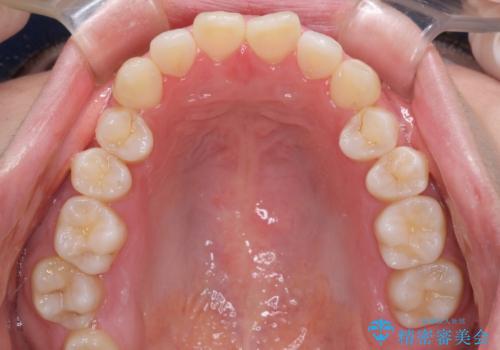

- 前歯のデコボコやクロスバイト、口元の突出感を気にして来院された患者様です。

上下左右の第一小臼歯4本を抜歯して、ワイヤー装置にて矯正治療を行うこととしました。

途中出産や育児があり、治療期間長くなってしまいましたが、ストレスなく唇が閉じられるような口元に仕上げることができました。